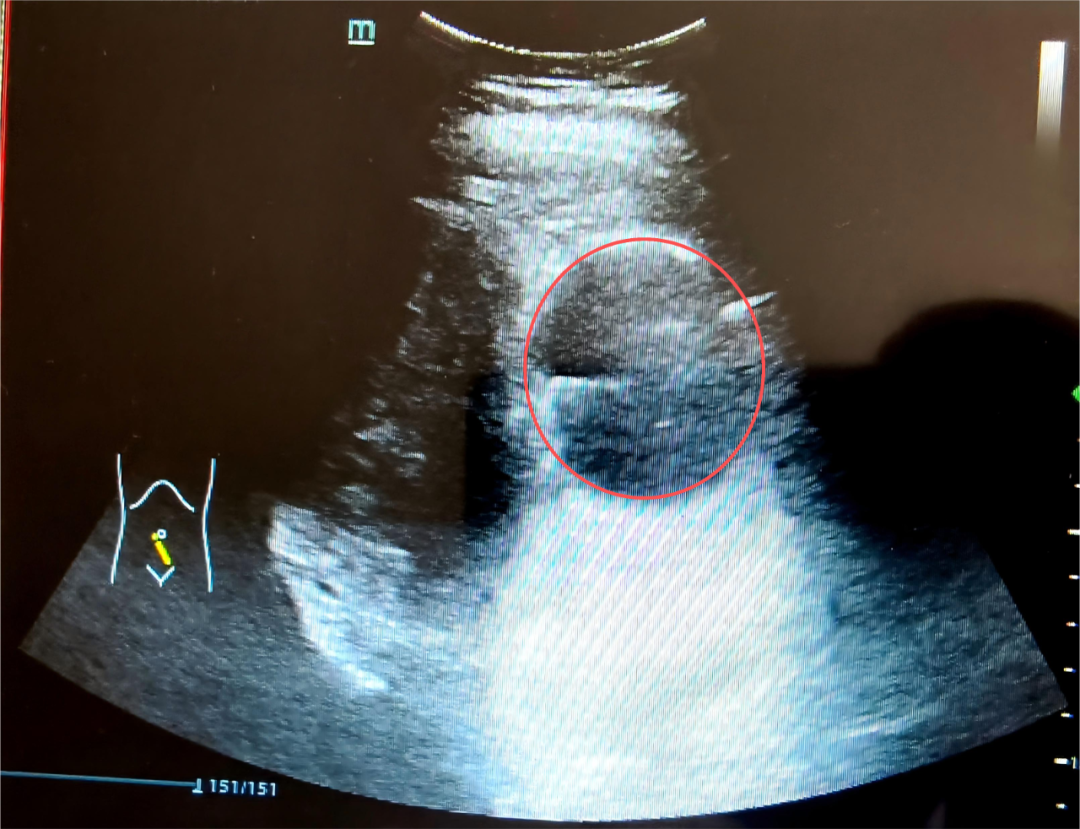

彩超提示:孕妇宫体肌壁可见一个异常回声结节,大小约83mm*72mm*83mm(前壁下段)。